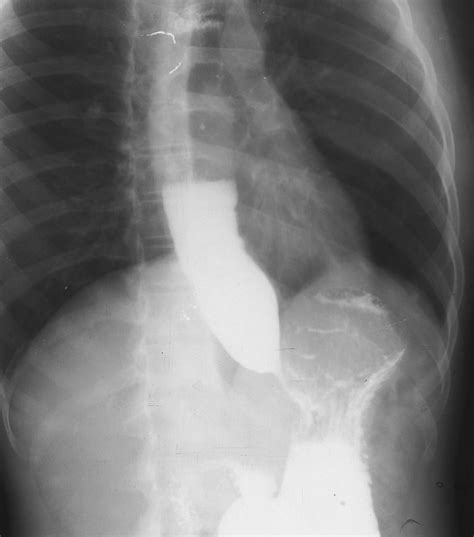

The hallmark finding on a barium swallow study for achalasia is the "bird’s beak" appearance. This occurs because the LES remains tightly closed, causing the esophagus above it to dilate and taper to a narrow point, resembling the beak of a bird. This visual evidence is often the first major indicator that confirms a diagnosis of achalasia.

Achalasia is a relatively rare, chronic disorder of the esophagus that makes it difficult for food and liquid to pass into the stomach. It occurs when the nerves in the esophagus become damaged or degenerate, preventing the lower esophageal sphincter (LES)—the muscular valve at the bottom of the esophagus—from relaxing properly during swallowing. Additionally, the normal rhythmic contractions of the esophagus, known as peristalsis, are lost.

Because the food cannot move efficiently into the stomach, it accumulates in the esophagus, leading to: